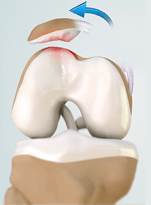

- Mais de 200 cirurgias artrocópicas do joelho por ano.

- Mais de 150 reconstrucções do ligamento cruzado por ano.

- Mais de 200 próteses do joelho por ano.